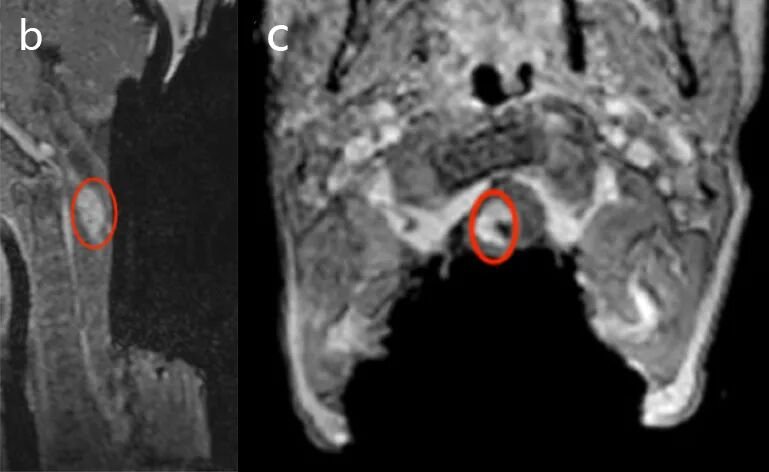

然而术中MRI检查结果显示,右侧C1-C2水平仍有少量肿瘤残留。手术继续实施,巴教授对这些区域残余肿瘤再次切除。术中MR检查后证实病变已完全切除。最后为确保患儿术后正常行动能力,巴教授还实施颅骨成形术及椎板原位复位术。